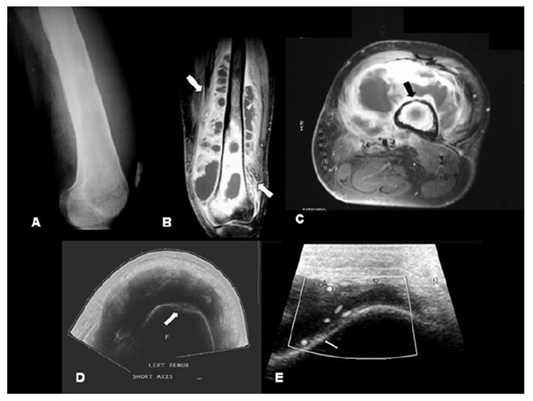

In case of osteomyelitis, the previous changes seen are swelling of soft tissue and low bone density. It is difficult to make the diagnosis of osteomyelitis in adults without observing suspected clinical manifestation along with the lab findings and radio imaging.23 Radiographs will generally not indicated until at least 50 to 75% of bone matrix is devastated. Infected area usually appears black (Figure 3). In contagious focus osteomyelitis, radiograph changes are indirect and require careful clinical to have diagnostic significance. Similarly, radiographic hints of improvements may delay behind clinical recovery.24 Ultrasound also detects the feature of osteomyelitis. Chronic osteomyelitis related to tissue abscess is recognized around the bony contours as anechoic fluid collection and also appear on ultrasound (Figure 3). Image A, showing the radio graph of left femur of with increased density and obliteration of tissue planes. Indicated arrow of image B and C represent the extensive soft tissue abscesses with T1-weighted MRI scans, while C image showing displacement of the soft tissues due to a bacterial abscess nearby to an irregular femoral cortex and last image indicate the Long axis vision of the femur.

Figure 3 Osteomyelitis due to direct implantation in a patient.